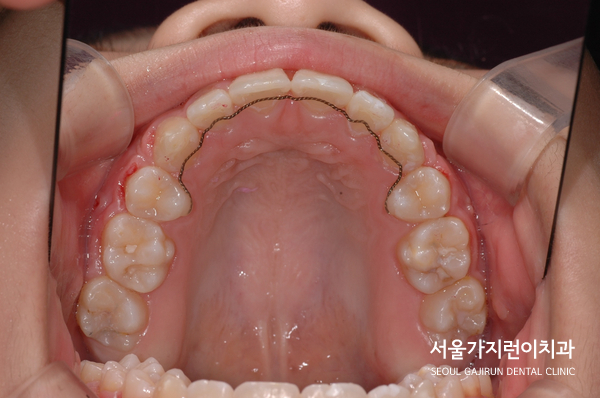

치료가 진행 되고 있을 때 찍은 사진인데요. 환자분의 경우 상악 치아가 하악 치아를 약간 덮고 있는 정상적인 교합으로 돨온 것을 확인할 수 있었습니다. 비뚤어진 치열도 말끔하게 배열되었는데요. 이와 동시에 무턱 증상도 많이 개선되어 교정이 끝난 후 4년 6개월간 안정적으로 유지된 것을 볼 수 있었습니다.